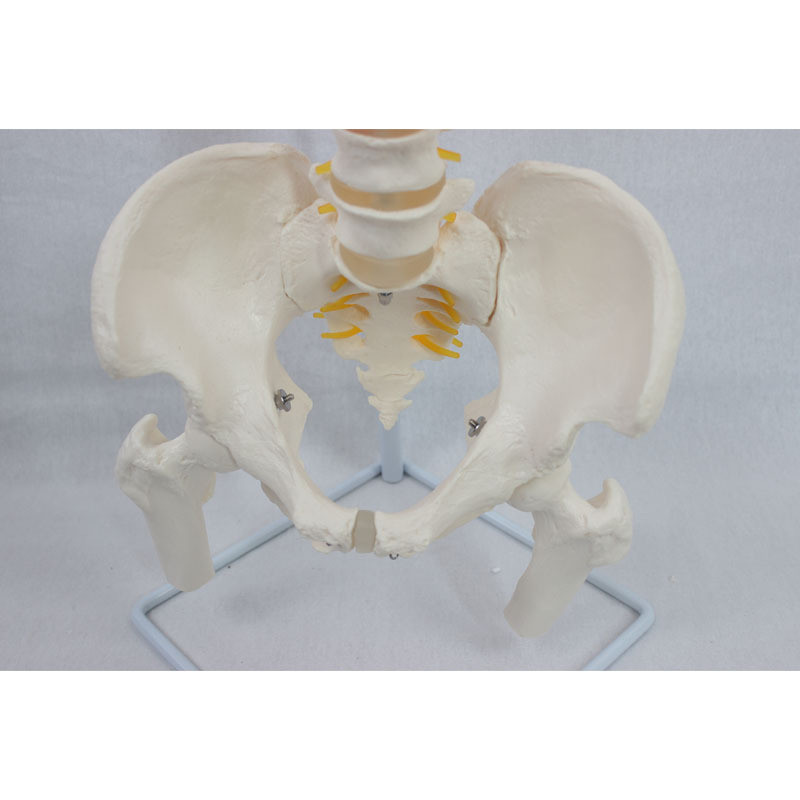

自然大脊椎枕骨和新骨盆带股骨模型 人体脊椎模型